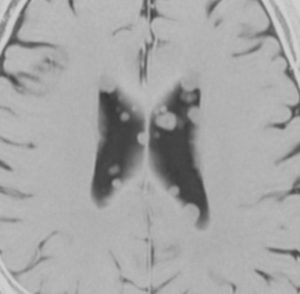

症候性の大きなSEGA

水頭症で発症した10歳の男の子のSEGAです。左側脳室の前角という部位から発生しました。腫瘍は右の脳室にものう胞を形成して,両側のモンロー孔を塞いだために閉塞性水頭症になって,頭痛と嘔吐が出ました。腫瘍の前方には腫瘍内出血もあります。